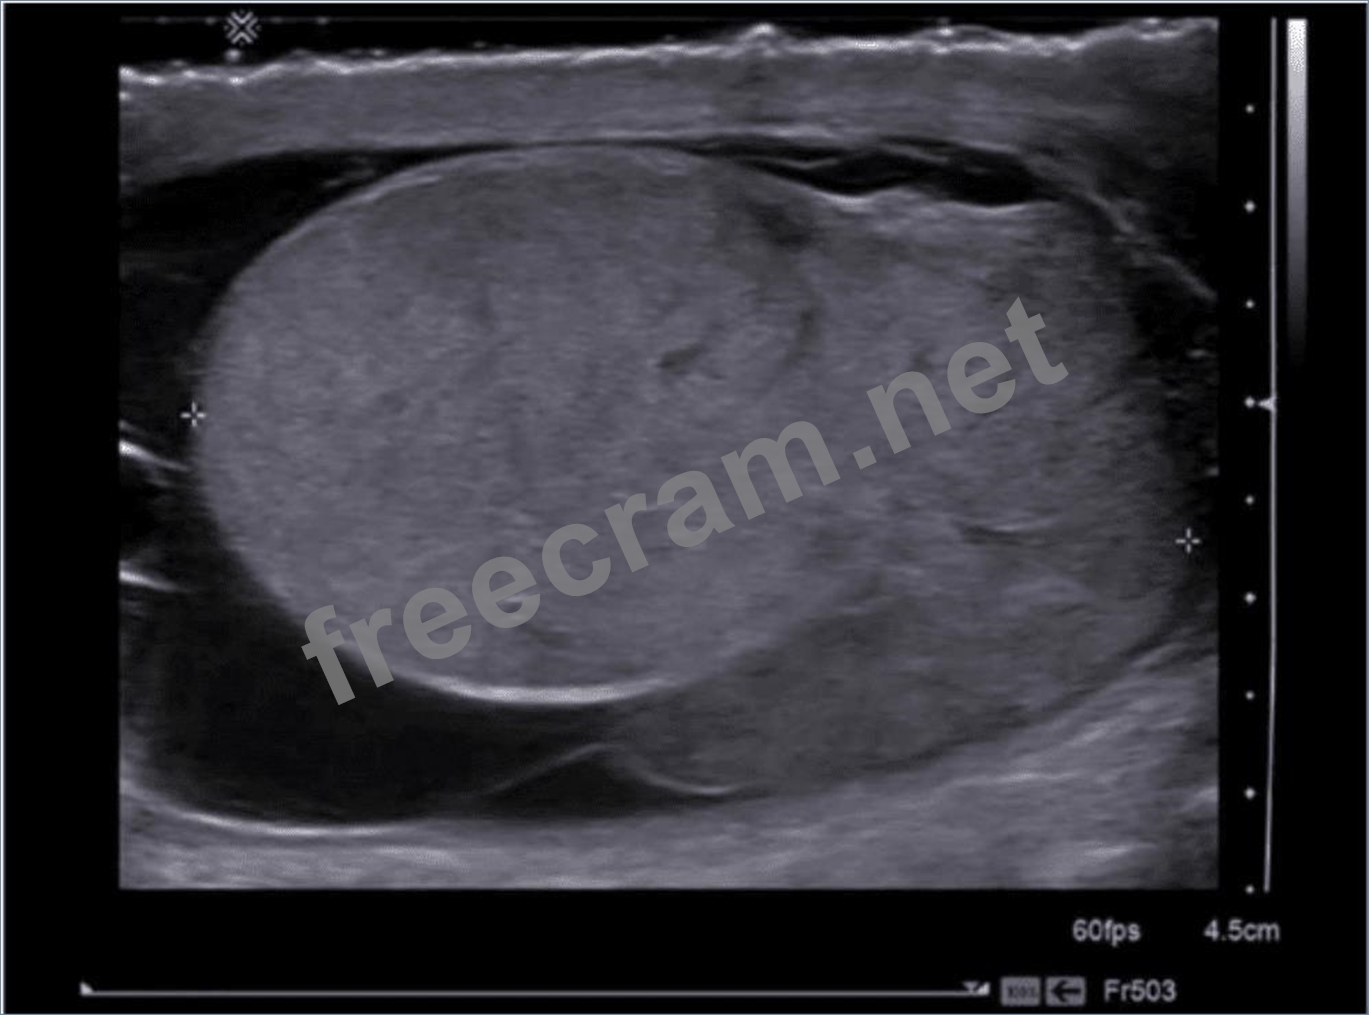

Which diagnosis is most consistent with this image from a patient with acute scrotal pain?

Question 22: Which diagnosis is most consistent with this image from a pa...